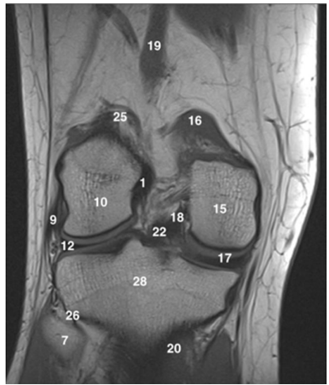

Observe a imagem a seguir.

Os números 10, 17 e 28 na ressonância magnética acima indicam as seguintes estruturas: